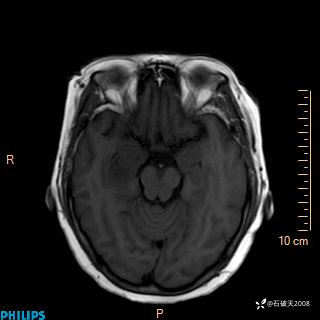

颅内占位,影像征象不是很丰富,有病理

hyy838 推荐女 62岁 主 诉:头晕12小时,加重1小时。

现病史:患者于12小时前无明显诱因出现头晕,呈持续性,无天旋地转及行走不稳,伴恶心、呕吐,呕吐共5次,呕吐物为胃内容物(具体性质不详),无胸闷、胸痛、心慌,无腹痛、腹泻,无咳嗽、咳痰,无发热、意识不清、肢体抽搐及大小便失禁等,1小时前患者上述症状加重,未诊疗,为求进一步治疗急自行来我院,门诊以“头晕待查”为诊断收入我科,发病来,神志清,精神差,饮食、睡眠差,大小便正常,体重未见明显下降。

FILAR